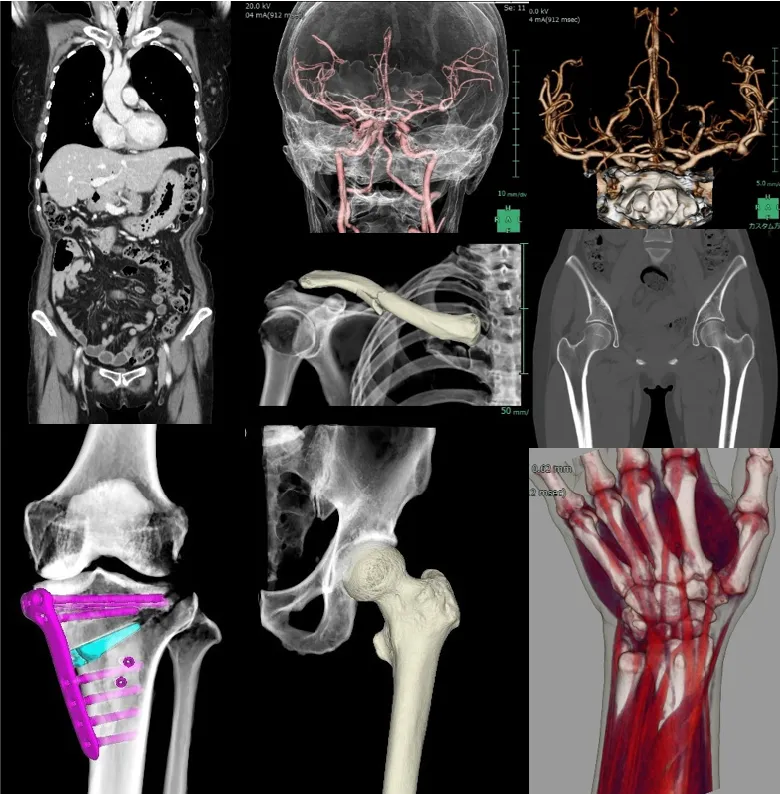

GEヘルスケア社製 64列CT

【Revolution Maxima】

当院では、2025年5月に最新の64列マルチスライスCTを導入しました。CT(Computed Tomography)装置はX線を用いて体の断面を撮影する検査機器で、頭頚部、胸部、腹部、四肢など全身の検査に対応しています。特に、胸部では大動脈や気管支、肺、腹部では肝臓や腎臓などの病変の描出に優れています。当院では、全身領域の検査を実施しており、高度な画像処理により任意の断面や立体的な3D画像を作成することが可能です。そのため、病変の診断だけでなく、手術計画や治療方針の決定にも役立っています。

GEヘルスケア社製 Revolution Maxima の特徴

当院の64列マルチスライスCTは、天井に設置されたAIカメラにより、患者さま一人ひとりに最適なポジショニングを自動で計画し、最も効果的なCT検査を実現します。また、最新のフルデジタル検出器と逐次近似再構成(ASiR-V)を搭載しており、従来のCTと比べて被ばく線量を大幅に低減することが可能です。さらに、目の水晶体など放射線の影響を受けやすい臓器には、正面方向からの直接被ばくを40%軽減するODM(Organ Dose Modulation)機能を備え、安全性にも配慮しています。加えて、従来CTでは体内金属によるアーチファクト(画像の乱れ)が診断の妨げになることがありましたが、SMART MAR(金属アーチファクト低減)機能により、インプラントやクリップ、プレートなどの周囲でもアーチファクトを低減し、より診断能の高い画像を提供できるようになりました。